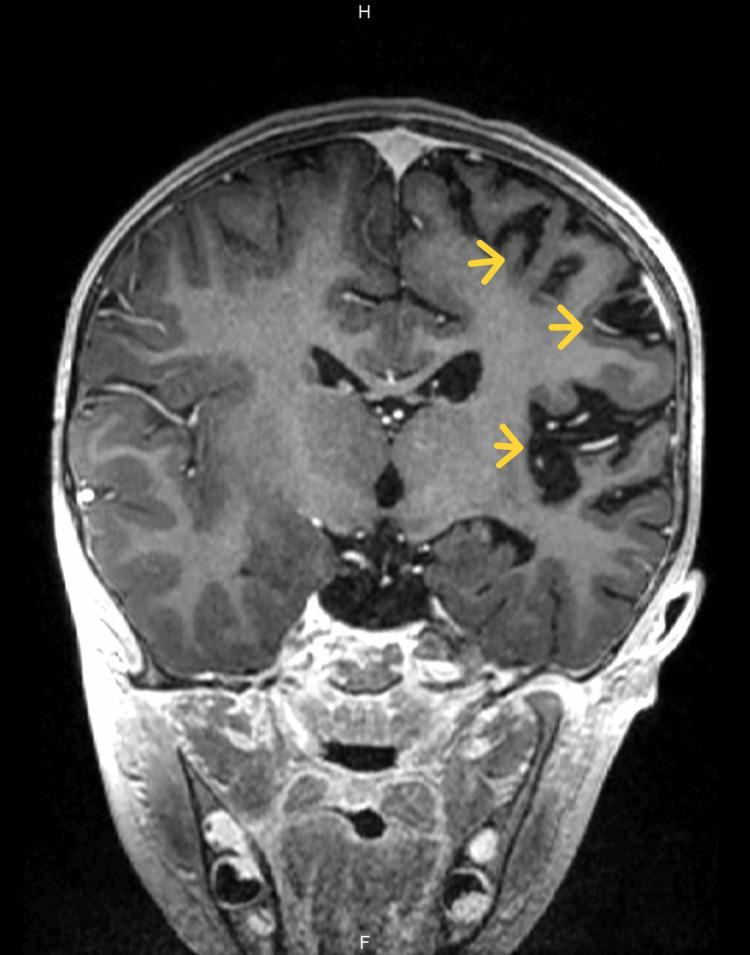

A three-year-old female patient was admitted to our institution due to subacute fever, intermittent vomiting, persistent bilateral mydriasis after cycloplegia, right central facial palsy, and mild right hemiparesis with hyperreflexia. Brain MRI shows encephalitis in frontal, parietal, insular, and left putamen course and loss of cortical volume and white matter of the entire left hemisphere which are features described in Rasmussen's encephalitis (RE). Therapy with intravenous methylprednisolone bolus was initiated, with adequate clinical response. We consider in this case the diagnosis of atypical RE by imaging criteria in the subacute stage. There are few reports of atypical RE without epilepsy or continuous partial epilepsy. Our purpose is to present a case of a patient with RE images without epilepsy seizures and review the diagnostic and therapeutic approach of RE.

摘要

一名三岁女性患者因亚急性发热、间歇性呕吐、睫状肌麻痹后持续性双侧瞳孔散大、右侧中枢性面瘫以及伴有反射亢进的轻度右侧偏瘫入住我院。脑部磁共振成像显示额叶、顶叶、岛叶及左侧壳核部位存在脑炎,且整个左半球皮质体积和白质减少,这些都是拉斯穆森脑炎(RE)所描述的特征。开始采用静脉注射甲泼尼龙冲击治疗,临床反应良好。我们根据亚急性期的影像学标准考虑该病例为非典型RE。关于无癫痫或持续性部分性癫痫的非典型RE报道较少。我们的目的是呈现一例无癫痫发作的RE影像患者病例,并回顾RE的诊断和治疗方法。